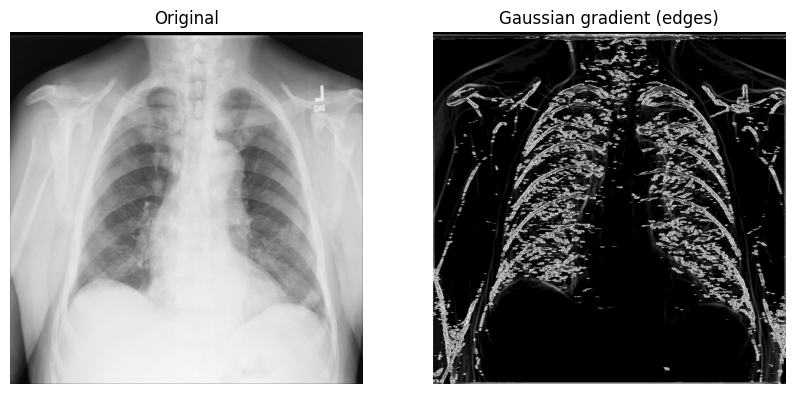

The Gaussian gradient magnitude method¶

Another method for edge detection that can be useful is the Gaussian (gradient) filter. It computes the multidimensional gradient magnitude with Gaussian derivatives and helps by remove high-frequency image components.

1. Call scipy.ndimage.gaussian_gradient_magnitude()

with a sigma (scalar) parameter (for standard deviations; you’ll use 2 in the

example below):

x_ray_image_gaussian_gradient = ndimage.gaussian_gradient_magnitude(xray_image, sigma=2)2. Display the original X-ray and the one with the Gaussian gradient filter:

fig, axes = plt.subplots(nrows=1, ncols=2, figsize=(10, 10))

axes[0].set_title("Original")

axes[0].imshow(xray_image, cmap="gray")

axes[1].set_title("Gaussian gradient (edges)")

axes[1].imshow(x_ray_image_gaussian_gradient, cmap="gray")

for i in axes:

i.axis("off")

plt.show()